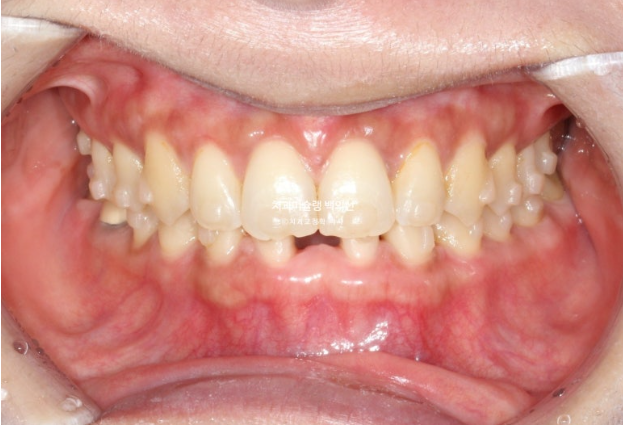

교정치료를 위해 내원한 환자분입니다. 아래 앞니 두 개가 없어서 이 사이 벌어짐을 치료하고자 오셨습니다.

윗니가 아랫니를 깊게 덮는 과개교합도 보입니다.

과개교합은 소량 개선되었고 아래앞니 공간은 가운데로 잘 모아졌습니다.

아래 정가운데 앞니 이외에 다른공간은 모두 닫혔습니다.